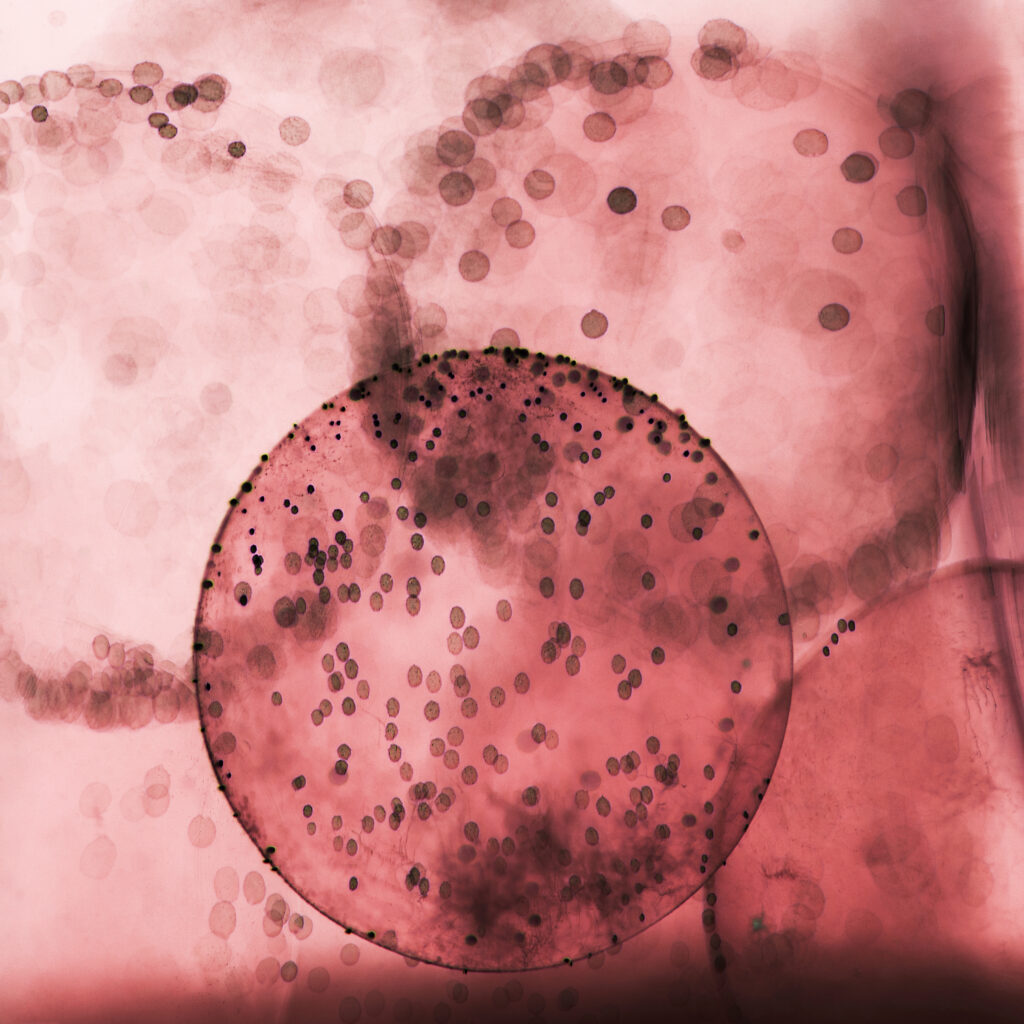

John, aged 44, first visited his GP complaining of a painful, red right eye with blurred vision, light sensitivity and a foreign body sensation that had started suddenly two days earlier. The GP noted conjunctival injection and a small corneal abrasion but prescribed antibiotic eye drops and advised follow-up if symptoms did not improve within 48 hours. No referral to ophthalmology was made at this stage.

Over the next 36 hours John’s symptoms worsened dramatically — severe pain, significant vision loss, purulent discharge and increasing photophobia. He returned to the same GP practice the following day. Medical negligence began here: the rapid progression of symptoms, severe pain and purulent discharge should have triggered an urgent same-day referral to an ophthalmologist rather than continued treatment with topical antibiotics alone.

The GP again reassured John that this was likely a bacterial conjunctivitis or worsening abrasion and added oral antibiotics without arranging specialist assessment. Medical negligence in failing to recognise the red flags of microbial keratitis (severe pain disproportionate to clinical signs, rapid vision loss, purulent discharge) allowed the infection to progress unchecked.

Rapid Deterioration and Delayed Specialist Care

Within 24 hours of the second GP visit John’s vision in the right eye had deteriorated to hand movements only. He attended A&E where an ophthalmologist finally examined him and diagnosed severe bacterial keratitis with corneal ulceration and hypopyon. Urgent treatment with intensive topical antibiotics, cycloplegics and admission was commenced, but the delay caused by medical negligence had already resulted in extensive corneal scarring and profound vision loss.